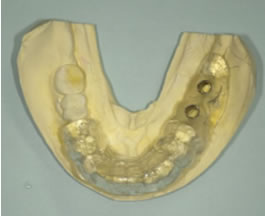

サージガイドの作成

サージガイド

アバットメントプロビショナルレストレーション含む